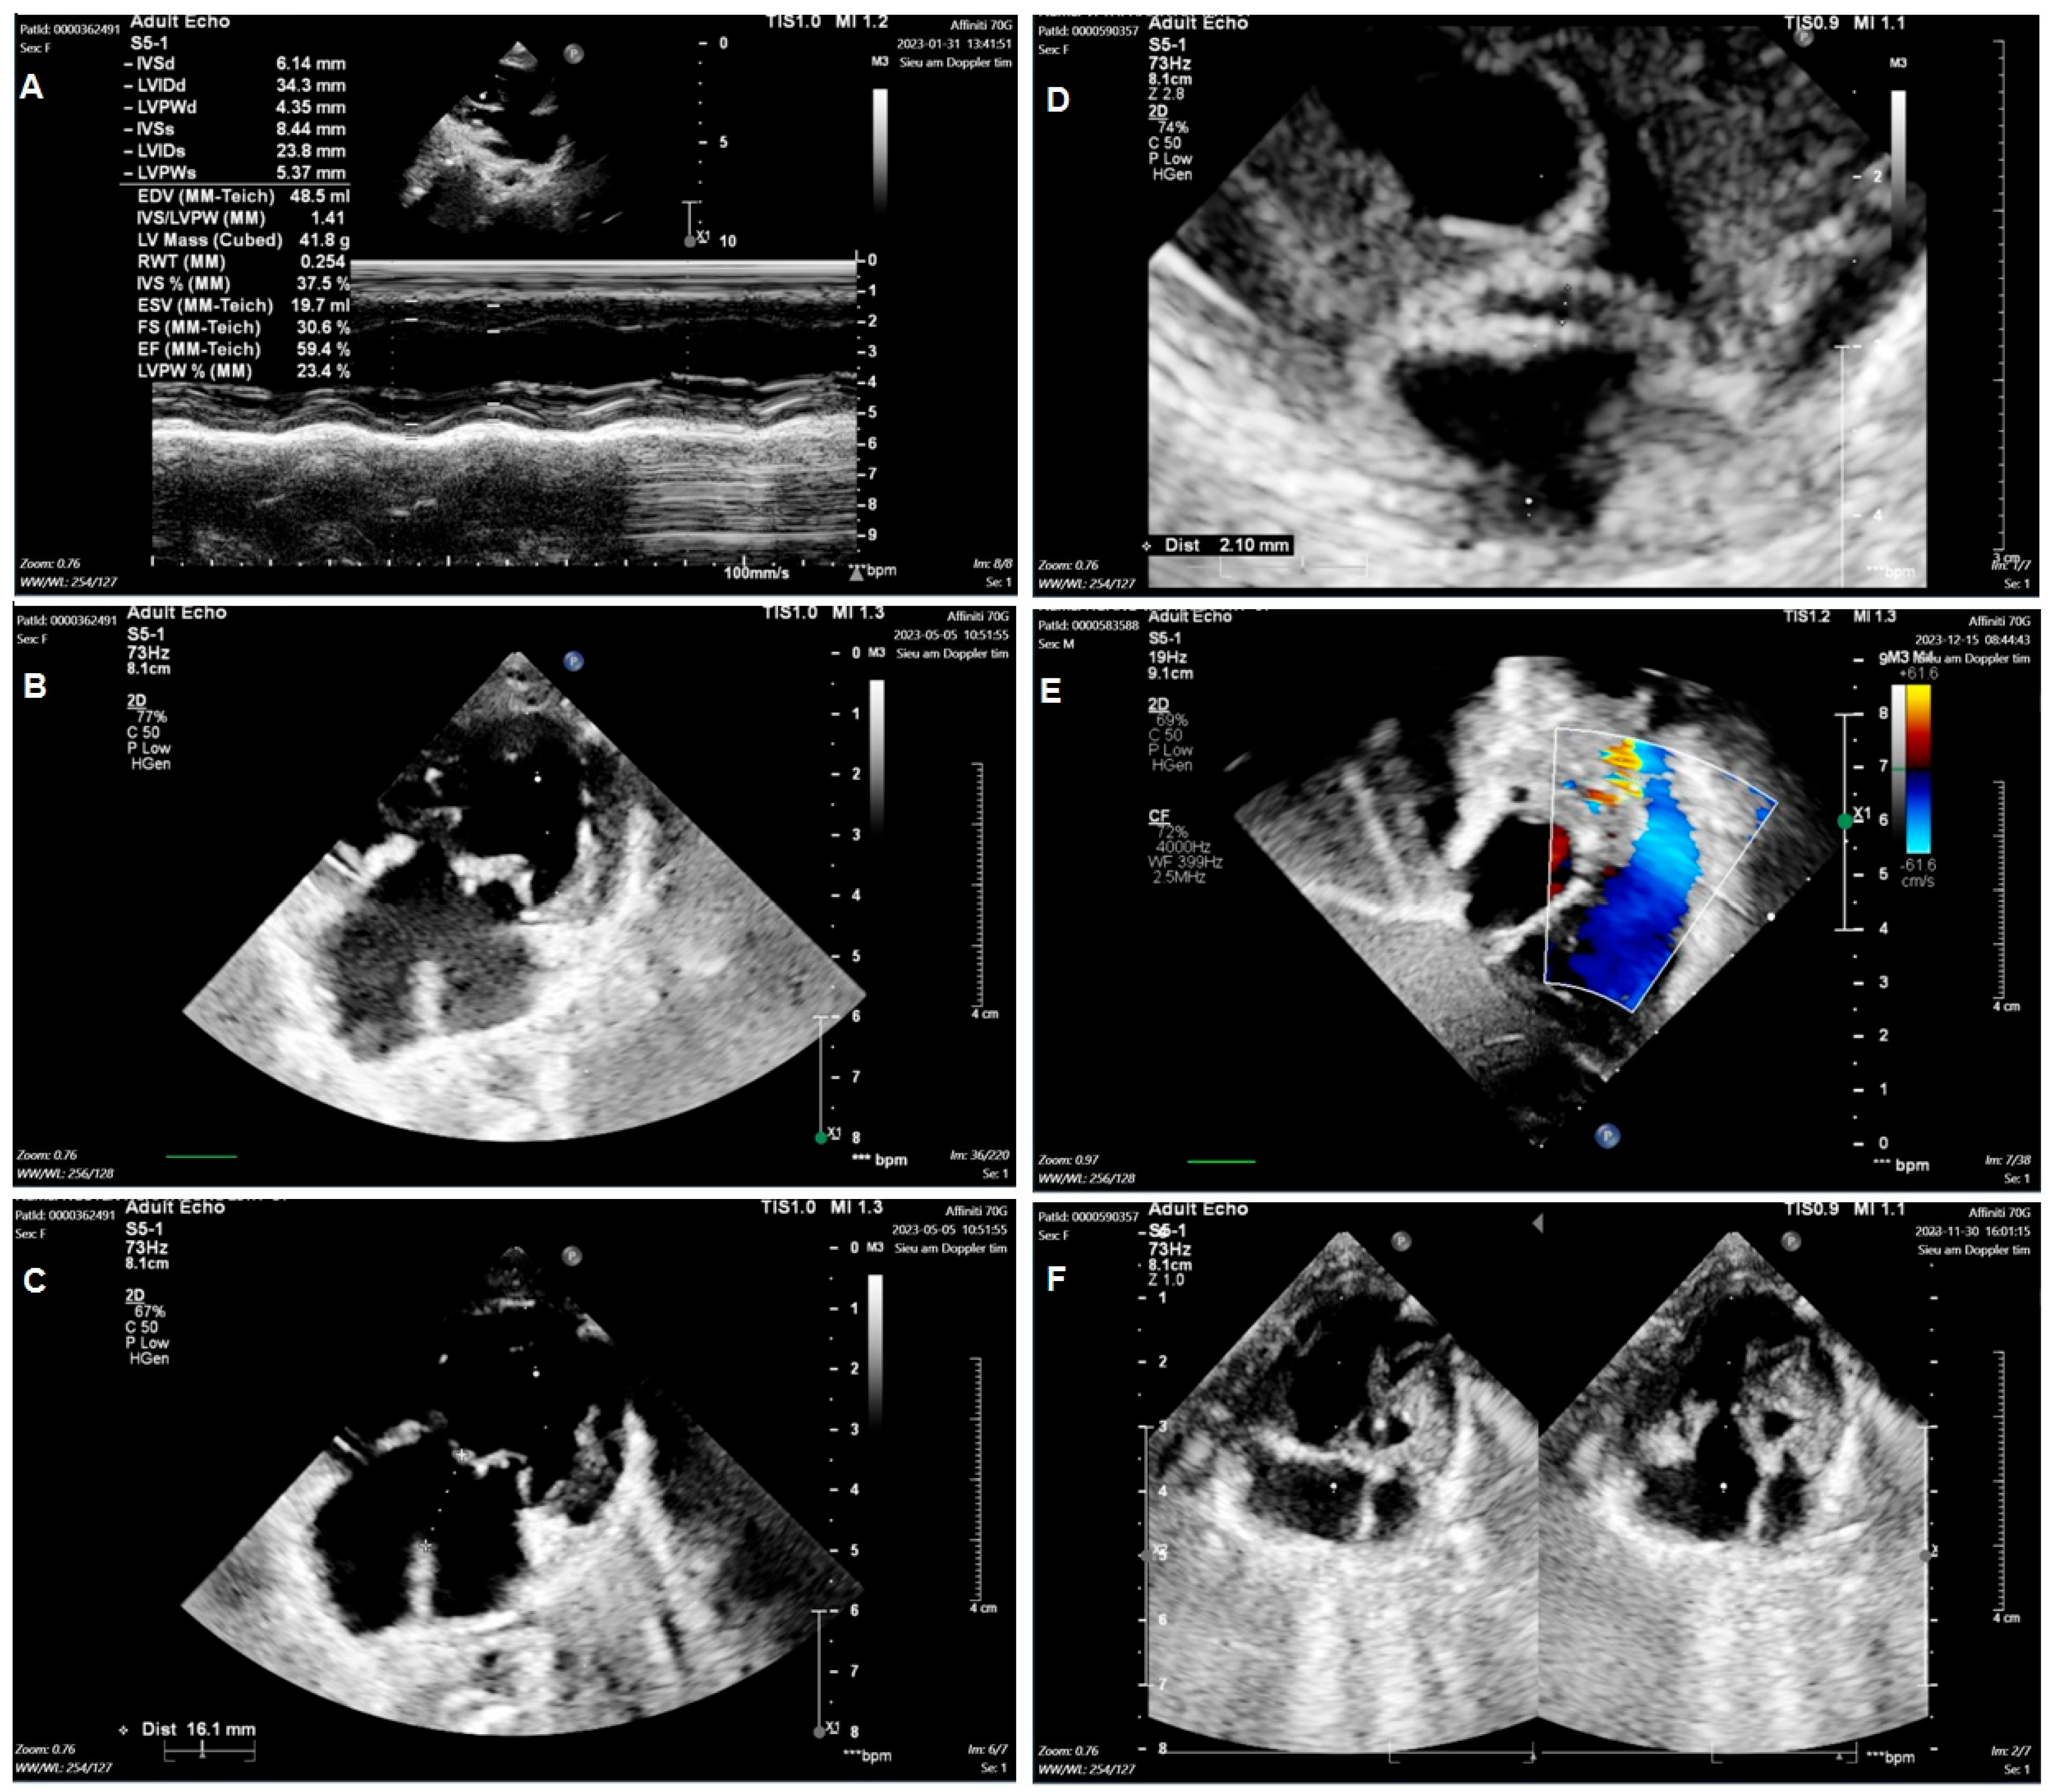

Group 1: Include nine TA patients with clinical features such as ASD, VSD, and PVS/PS (Figure 1A–C). The patients may have hypoplastic right ventricular, right ventricular outflow tract obstruction (RVOTO), DORV, TGA, and PDA. Group 2: Include three mitral valve atresia patients with clinical features such as hypoplastic left ventricular and DORV. The patients may have atrioventricular discordance, PDA, ASD, VSD, and TGA (Figure 1D–F). Group 3: Include twelve DORV patients with clinical features such as CAVSD and PVS/PS (Figure 2A–C). The patients may have a single atrium heart, a single ventricle heart, AAH, AS, ASD, VSD, TGA, and a total anomalous pulmonary venous connection (TAPVC). Group 4: Include five HLHS patients with clinical features such as AAH, AS, BAV, ASD, VSD, and PDA (Figure 2D–F).

Figure 1. Echocardiogram in the patient with tricuspid valve atresia and in the patient with mitral valve atresia. Including the image of Tricuspid valve atresia (A); Ventricular septal defect (B); Atrial septal defect (C); Mitral valve atresia (D); Ventricular septal defect (E); Atrial septal defect (F) in patient.